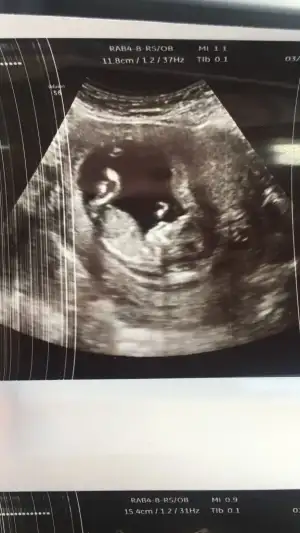

Yaa maşallah ne kadar tatlı gözüküyoo içerde de keyfi çok yerinde belli annişiHamis anneler selam. Ben de bugun kontrole gittim 12+6 yım herseyi normal, kendimi bildim bileli hep kız isterdim ama hamileligimi ogrendigimden beri erkek hissediyodum doktor %80 erkek deditabikii sevindim kiz olsaydi ciglik atardim orasi ayri , benden fazla sevinen taraf esim oldu :))) bide biraz fazla rahatti bizimki bacak bacak ustune falan atmisti

Aramizda 1 hafta varmis 1 haftaya sen de ogrenirsin insallah :) kontrolun ne zamandı? Benimki gostermiyordu kapaliydi bacaklari doktor biraz ultrason cihaziyla dürttü jimnastik yapti hahaAa hayırlı olsun canımm ne güzel öğrenmişsin darısı başımızaTutturabildiğime de ayrı bi sevindim

Kıza benzettim benEki Görüntüle 2798000 İyi gecelerbugün bebitoyu gördük kocamaaan olmuşuz doktorumuz cinsiyet tahmini yapabileceğini söyledi ama ben netleşince söyleyin şimdi pat diye kesinmiş gibi hissederim dedim. Sizin bir tahmininiz var mı acaba

![]()